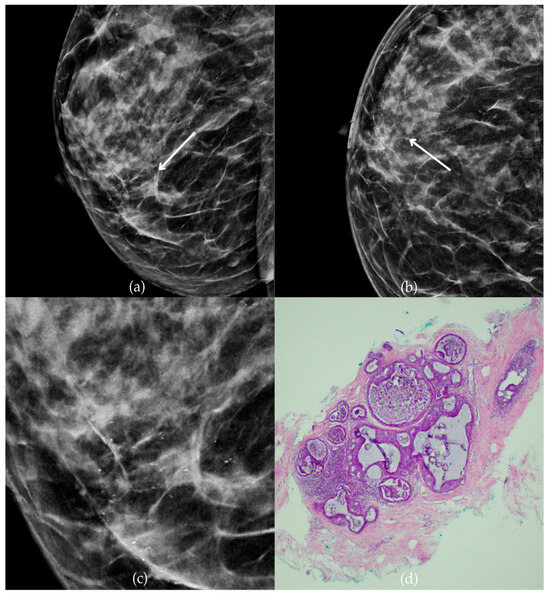

The mammogram and histopathological images (Figure 4) of the 62-year-old patient’s left breast show grouped coarse heterogeneous calcifications in the upper outer quadrant, corresponding to a BI-RADS 3 finding. Tissue analysis obtained through biopsy indicated the presence of an invasive carcinoma (category B5b). The patient underwent quadrantectomy, and postoperative pathology confirmed the diagnosis of invasive carcinoma. The patient’s most recent MRI, performed two years after the initial diagnosis, was assessed as BI-RADS 2, suggesting benign changes.

Invasive breast cancer. (a) Mediolateral oblique (MLO) mammography view; (b) craniocaudal (CC) mammography view of the left breast showing grouped coarse heterogeneous calcifications (marked with arrows) in the upper outer quadrant. (c) Magnified mammographic image of grouped coarse heterogeneous calcifications. (d) The histopathological image of the biopsy sample shows the characteristic features of invasive cancer (marked with arrow) and ductal carcinoma in situ (DCIS) (marked with arrowhead) (HE staining; 40× magnification).